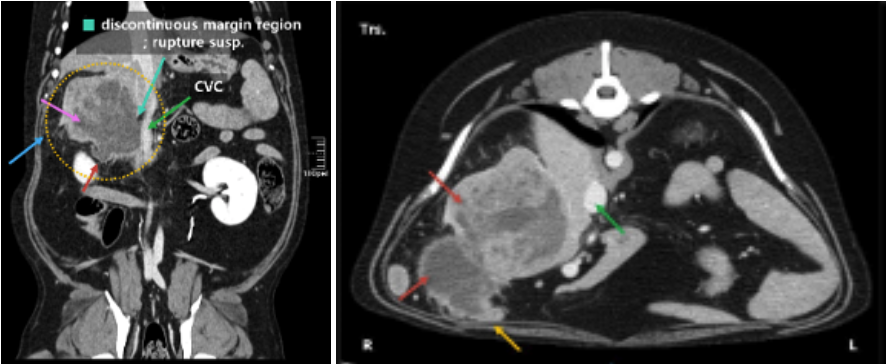

02 CT 검사로 확인된 8cm 간종양

CT 검사 결과, 종양은 간 꼬리엽(caudate lobe)에서 발생한 약 8cm 크기의 거대한 종양이었습니다.

강아지 간종양 CT 사진(약 8cm) / 출처: 에스동물메디컬센터

주의 깊게 보아야 했던 점은 종양이 대정맥(CVC)과 매우 인접해 있었고 중심부에 괴사로 보이는 저감쇠 영역이 존재했으며 부분 파열(partial rupture)이 의심되는 소견이 확인되었다는 점입니다. 또한 주변 장기들과의 유착 소견도 관찰되었습니다.

파열이 의심되는 간종양은 복강 내 출혈 위험이 높아, 상황에 따라 생명을 위협할 수 있기 때문에 신속한 수술적 처치가 필요한 상태였습니다.